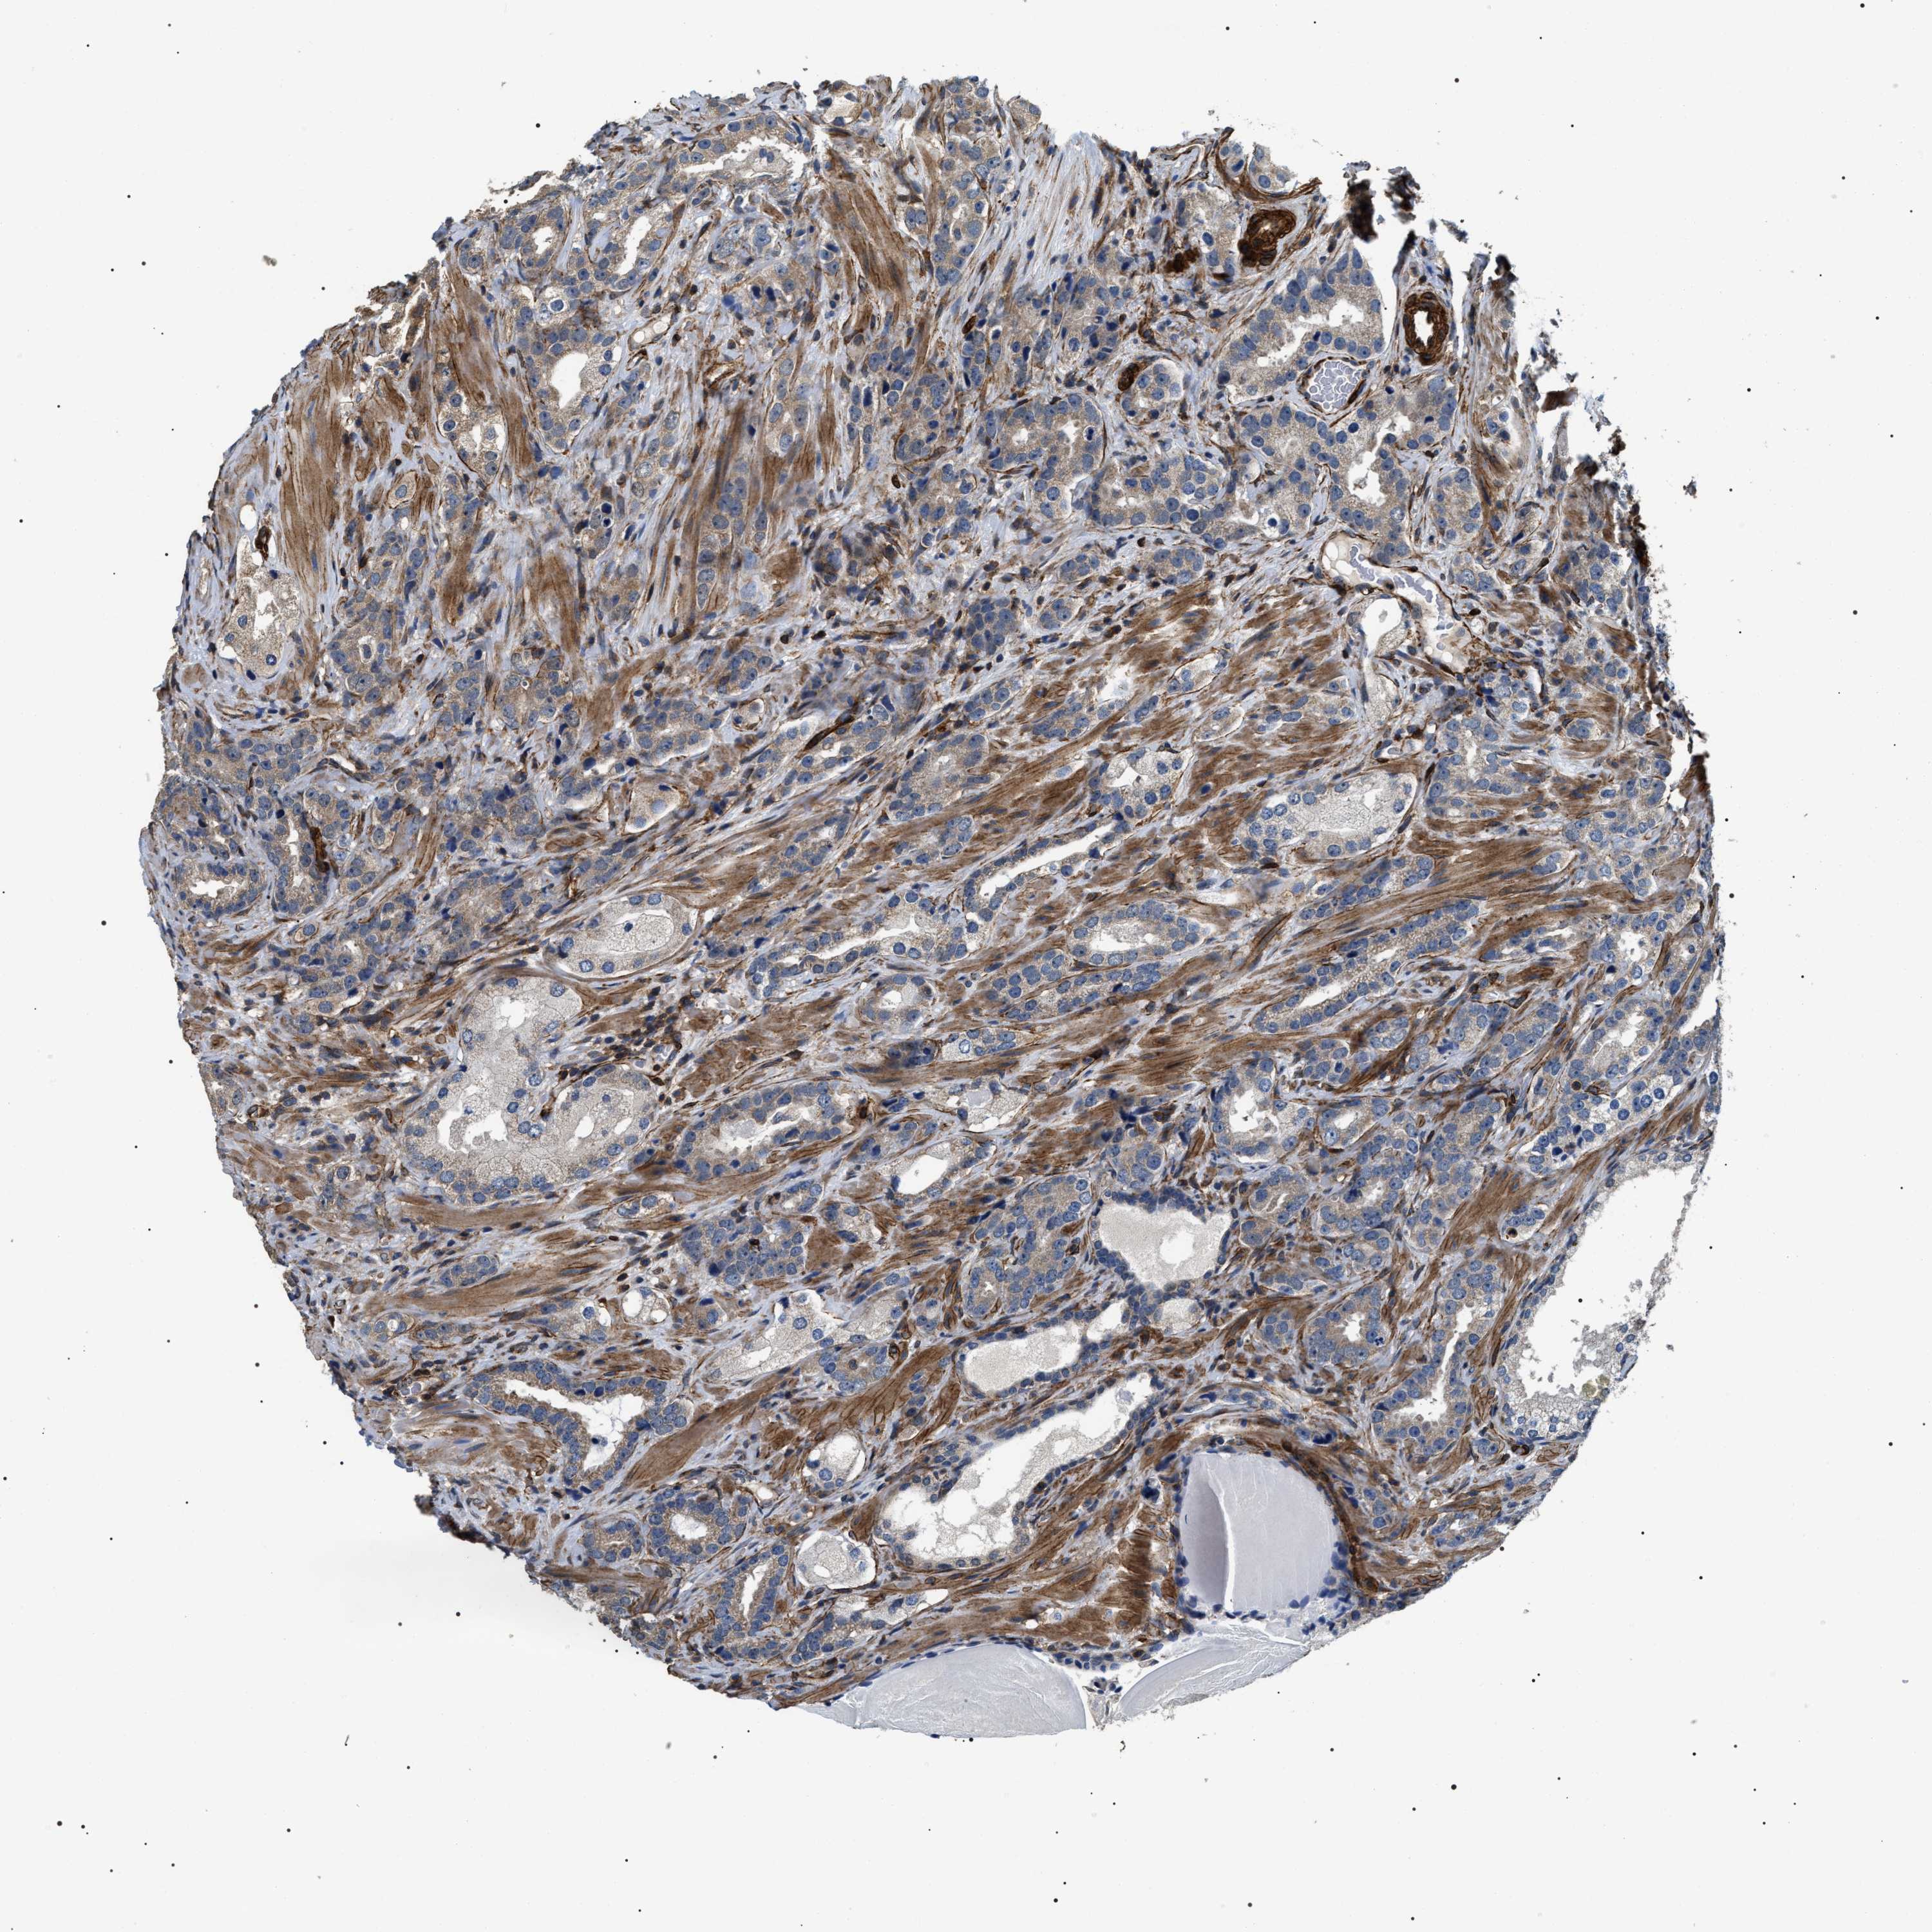

PROSTATE CANCER - Protein expressioni

A mouse-over function shows sample information and annotation data. Click on an image to view it in a full screen mode. Samples can be filtered based on level of antibody staining by selecting one or several of the following categories: high, medium, low and not detected. The assay and annotation is described here.

Note that samples used for immunohistochemistry by the Human Protein Atlas do not correspond to samples in the TCGA dataset.

Antibody stainingi

Antibody staining in the annotated cell types in the current human tissue is reported as not detected, low, medium, or high, based on conventional immunohistochemistry profiling in selected tissues. This score is based on the combination of the staining intensity and fraction of stained cells.

Each image is clickable and will lead to virtual microscopy that enables deeper exploration of all samples and also displays staining intensity scores, fraction scores and subcellular localization as well as patient and tissue information for each sample.

Antibody HPA020386

Staining

High

Medium

Low

Not detected

Intensity

Strong

Moderate

Weak

Negative

Quantity

>75%

75%-25%

<25%

None

Location

Nuclear

Cytoplasmic/membranous

Cytoplasmic/membranous,nuclear

Adenocarcinoma, High grade

Adenocarcinoma, Low grade